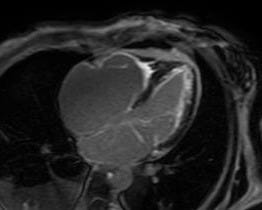

Imagem da semana

Ressonância magnética cardíaca em sequência de realce tardio ao gadolínio com a presença de fibrose subendocárdica difusa biventricular.